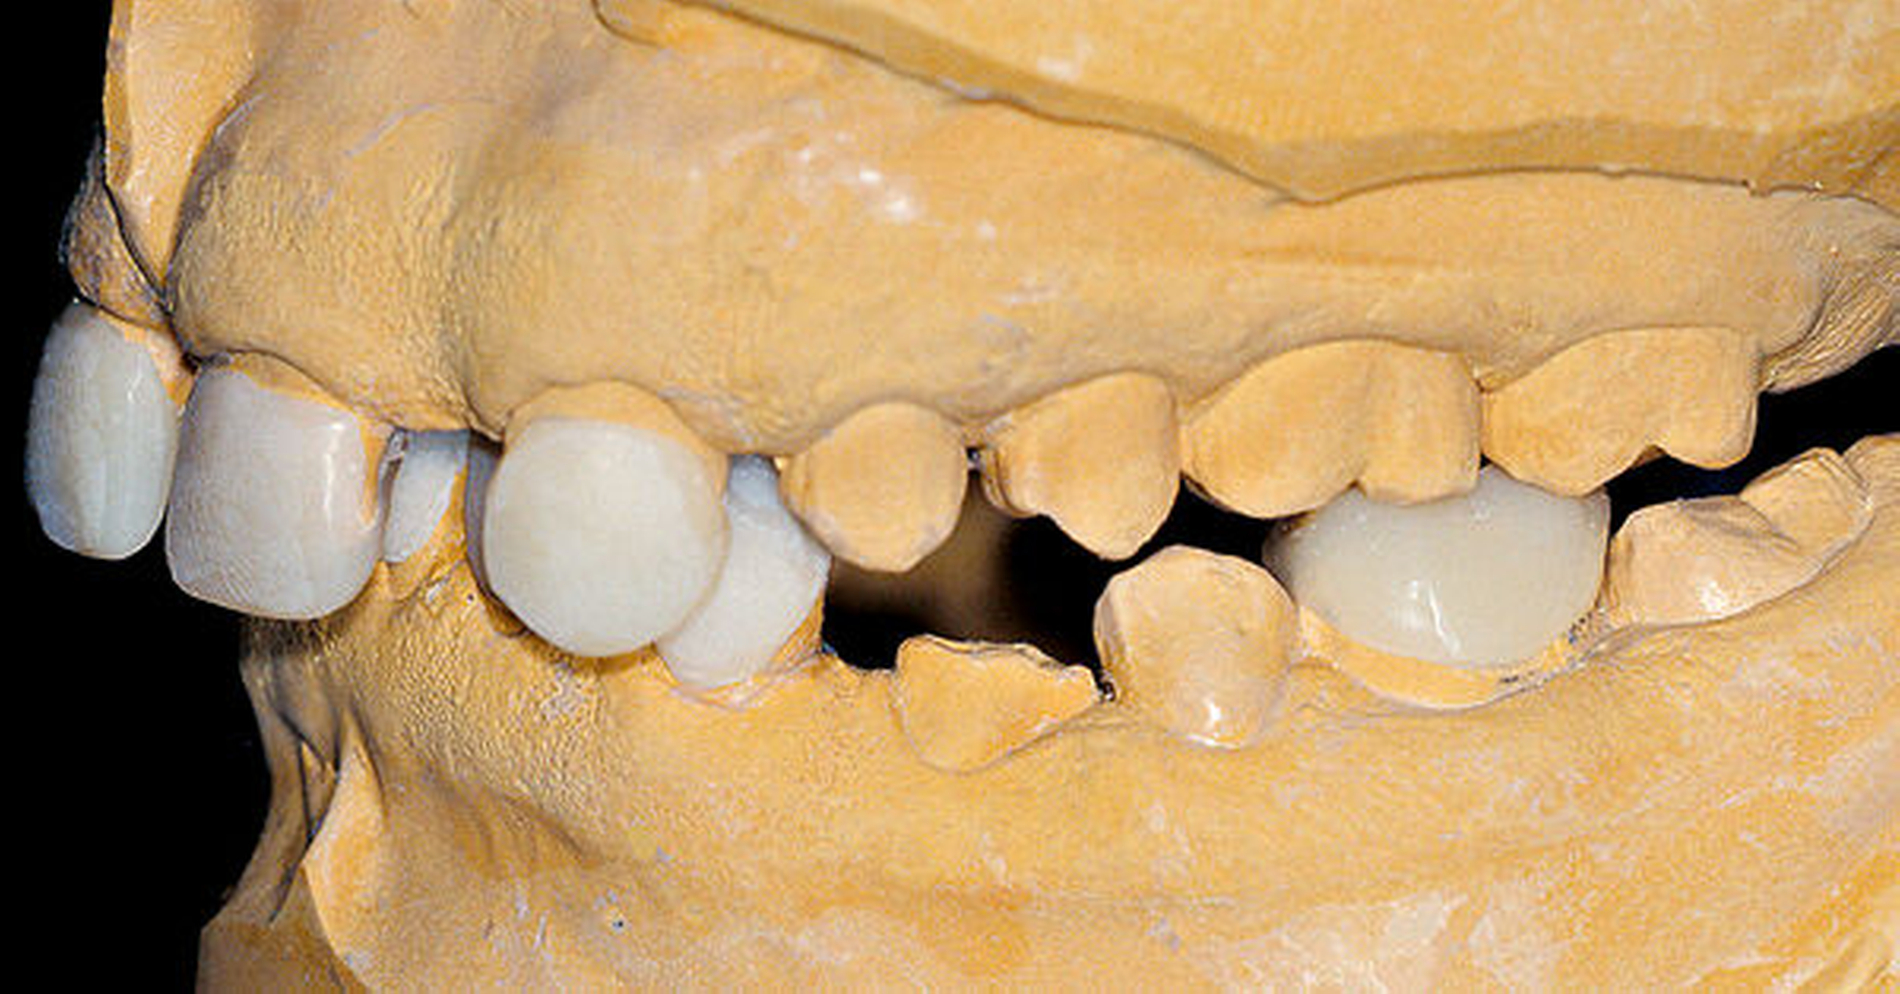

Unter Bisshebung auf Artikulator-montierten Modellen hergestellte Kunststoffprovisorien auf den Ober- und den Unterkiefer-Schneide- und -Eckzähnen und den Unterkiefer-Sechsern (Abbildung 5) wurden adhäsiv eingesetzt (Abbildung 6). Die so bewerkstelligte Vergrößerung der Zähne war Voraussetzung für die kieferorthopädische Behandlung.